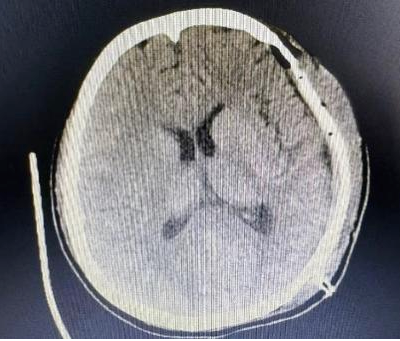

术后CT